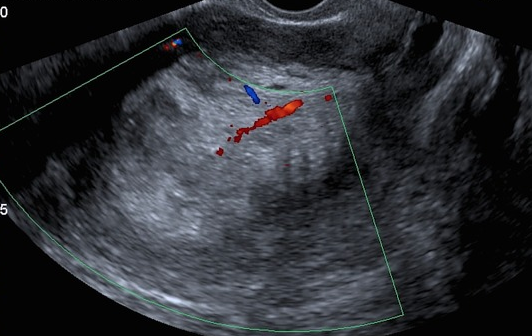

Carcinome de l'Endomètre US

endometre endometrial